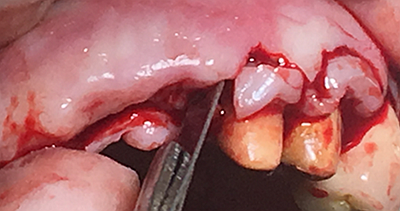

擴孔,檢查方向。

大家注意這個動作,雖然不翻瓣,但要將唇側(cè)倒凹處骨膜剝離。

植入植體。

將骨粉塞入剝離的骨膜下間隙里既唇側(cè)倒凹處,盡量塞滿。